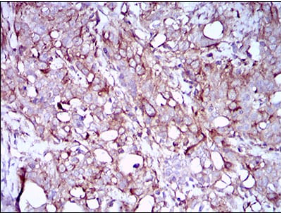

SYCP3 Mouse Monoclonal antibody[6F9C5]

IHC    1/200 - 1/1000